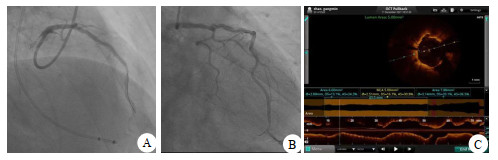

LAD一周后(12月11日)行旋磨:消毒,铺巾,穿刺右锁骨下静脉,置入临时心脏起搏电极(图 4A),单腔起搏方式60次/min起搏保驾。LAD狭窄与环状钙化处选1.25 mm旋磨头反复3次旋磨。OCT检查示,钙化结节消失,球囊反复扩张,狭窄明显好转,选2.75 mm×33.00 mm支架植入LAD病变处(图 4B),OCT检查有部分支架贴壁不良现象,再用后扩球囊反复扩张,再次OCT检查支架无膨胀不全及贴壁不良(图 4C),冠脉造影未见残余狭窄,FFR 0.94。11 d后康复出院,心肌酶趋势图显示恢复良好(图 2)。

| A为LAD 80%狭窄,FFR 0.76;B为旋磨后支架植入FFR 0.94;C为旋磨及支架植入后OCT检查无贴壁不良及膨胀 图 4 病例1的术后冠脉造影及OCT检查结果 |